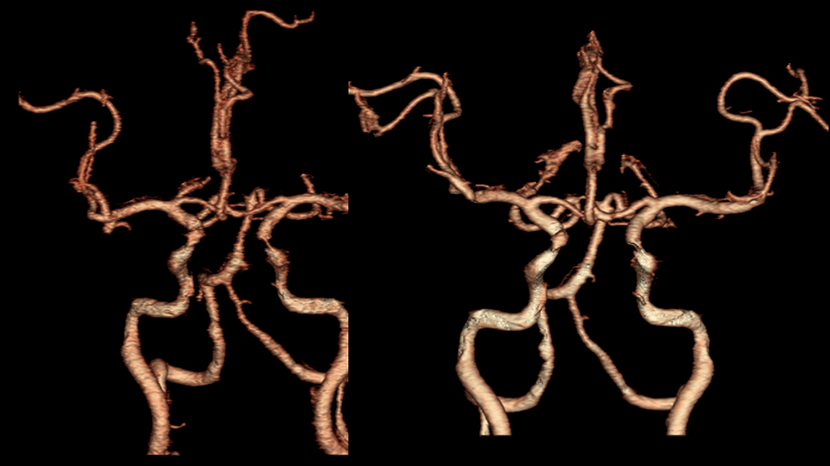

뇌MRA 와 뇌혈관조영술에서 좌측내경동맥의 심한 협착이 보임

성형술과 스텐트 삽입술을 시행하여, 우측의 수술전 사진과 비교시, 혈관을 넓혀주어 추가적인 뇌경색을 예방

CT혈관 조영술과 뇌혈관조영술에서 좌측 중대뇌동맥의 폐색이 보임

혈관내 수술 기법으로 혈관안에 있는 혈전을 제거

수술전 사진과 비교시, 사라졌던 혈행이 되살아남